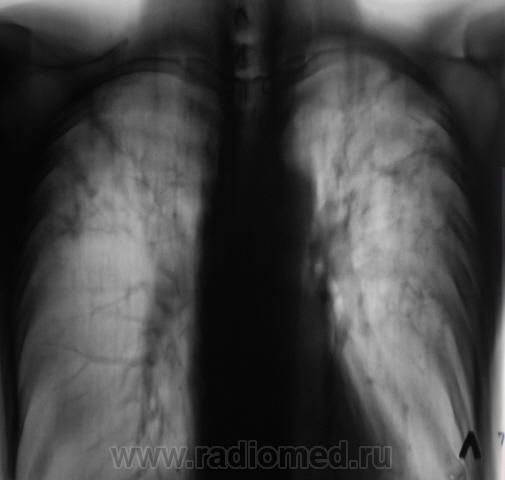

И, уже через год, при плановом обследовании данного пациента, мы "поимели" такие картинки.

Сомнения вызвала тень, помеченная желтой стрелкой. На наш взгляд, это был растущий гриб. Однако возобладало мнение, что "это" участок некроза, так как не было "симптома погремушки"

Однако, в последующем, лабораторно наличие "гриба" было доказано.

А, может быть, не стоит ожидать, когда появится типичный симптом "погремушки". Может, не стоит искусственно выращивать патологию?

Возможно, совершенно по-другому, стоит посмотреть на ранее представленный мною случай?

А, я же ничего и не утверждаю, я просто, задаю вопрос.  Нашли у этого пациента "грибы", и в большом количестве.